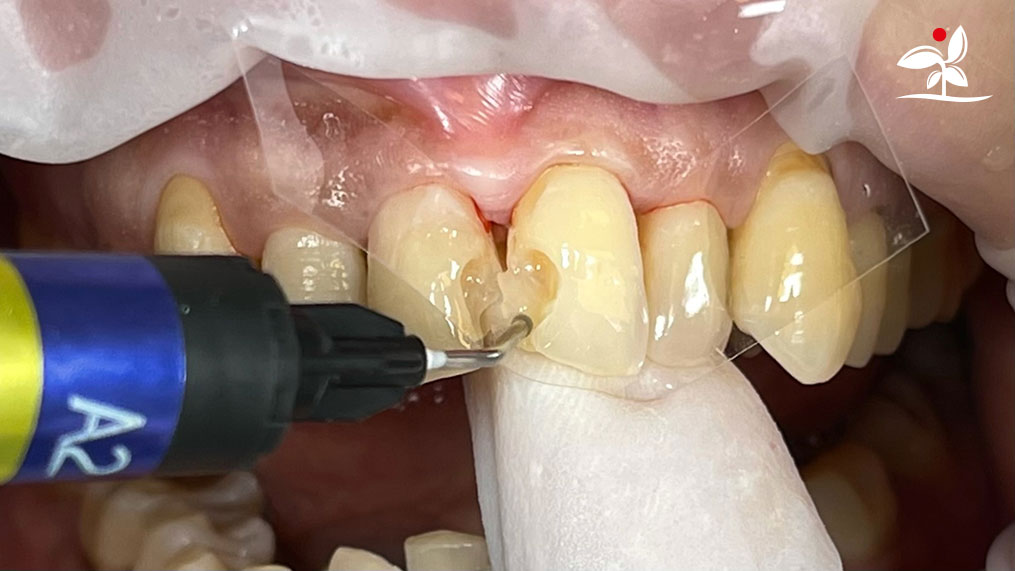

Restoration of Class IV Lesions using Naturomimetic Layering Technique (NLT) and Bioactive Restorative Materials

With the growing awareness about the health, function and aesthetic benefits of preserving natural tooth structure, patients are now globally demanding for aesthetic dentistry with minimally invasive procedures that has a low biological cost. This public demand has encouraged logical clinicians to adopt to the minimally invasive cosmetic dentistry (MiCD) concept and its treatment protocol [1] in their practice. The author has been using MiCD concept and its treatment protocols since 2017, which

include the methods of treatment that are simple, fast, predictable and healthy. In aesthetic restoration, the tooth color restorative materials placement technique is one of the most challenging, confusing and frustrating areas to learn owing to the multiple techniques that have been proposed by many clinicians and replicating such techniques in practice is not always as easy as they are marketed in dentistry. Natural teeth are complex in structure and hard to simulate due distribution of colors through enamel and dentin [2]. Aesthetic restoration strategies should follow proper understanding of defects, right selection of restorative materials along with their proper application, finishing, texturing and polishing [2].